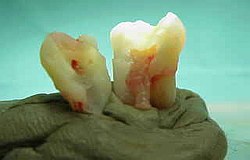

Der tote Zahn wird zur Darstellung des Nervs aufgebohrt

Wird nichts mehr empfunden so ist er tot und das tote Gewebe muss schnellstens aus dem Zahn entfernt werden (Wurzelkanalreinigung) bevor es im Zahn verfault und zu starken Schmerzen bis hin zur dicken Backe (Zyste) führt. Obwohl im Bild zur Verdeutlichung dargestellt ist eine Aufbereitung des Wurzelkanals (Nervnadel ragt über Wurzel hinaus ) über die Wurzel in den Kieferknochen bei der Zahnwurzelbehandlung natürlich nicht erwünscht. Um dies zu vermeiden müssen während der Wurzelbehandlung Röntgenaufnahmen angefertigt werden, die die ungefähre Länge der Wurzel berechnen lassen. Besser noch lässt sich die Länge der Wurzel elektronisch bestimmen .(Auf Wunsch Privatleistung). Ist die Wurzel an Ihrem Ende weit geöffnet kann es trotz aller Vorsicht zu einem ungewünschten Überaufbereiten und zu einer Überfüllung der Wurzel kommen. Dies beeinträchtigt dann oft den Erfolg. html Text zum Ausdrucken als pdf Datei. Falls über die Wurzelspitze hinaus in den umliegenden Knochen bereits Eiter aufgetreten ist und dieser den Knochen um den Zahn auflöst (das sieht man im Röntgenbild), so muss die infektiöse Wurzelspitze und die darum liegende Zyste entfernt werden .Im Prinzip ähnlich einem Pickel ausdrücken. Sobald der Druck (Eiter) dann heraus kann, geht sehr schnell der Schmerz bzw. auch die dicke Backe zurück. Der Vorgang nennt sich Wurzelresektion oder Apektomie. Die moderne Wurzelbehandlung umfasst Nickel-Titan-Feilen mit drehmomentregulierten Motoren gegen Instrumentenbruch, elektronische Längenmessung, Langzeit-provisorische Wurzelfüllungen mit provisorischen Langzeit-Füllungen. Alles leider Dinge die nicht in der Kassenleistung enthalten sind. So bleiben für den Patienten Kosten von ca. 60-480 EUR (je nach Schwierigkeit ) pro Kanal Aus manchen spezialisierten Prominentenpraxen wurde mir schon von Preisen bis zu 1200 EUR pro Kanal berichtet.